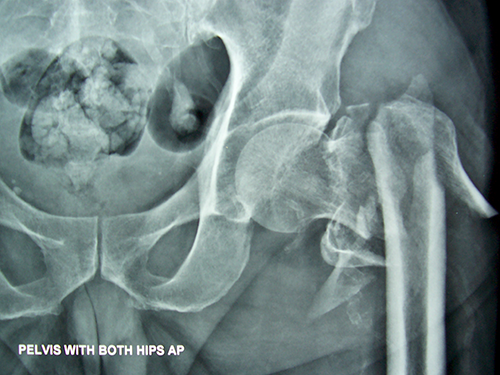

Case:10 Pathological Fracture

Seconderies from CA Prostate in 65 years old male patient treated with cemented bipolar prosthesis.

Pre-op

Post-op X-ray